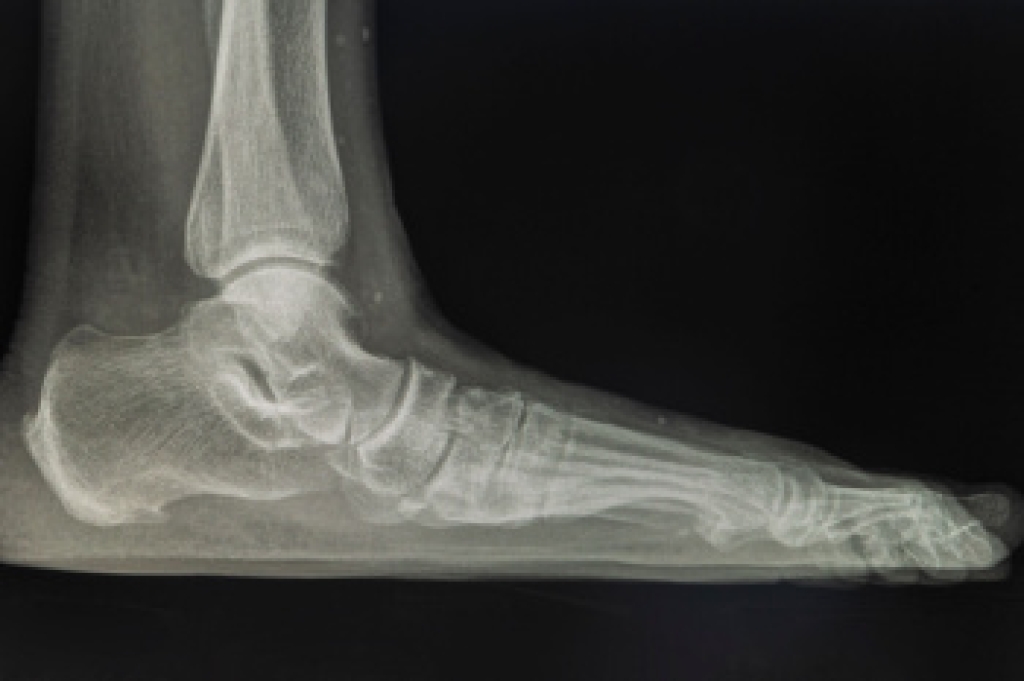

An ankle sprain occurs when the ligaments that stabilize the ankle stretch or tear, often following a twist, fall, or sudden blow to the joint. Ligaments connect bones together, and, when damaged, they can cause significant pain and limit mobility. Signs of an ankle sprain include swelling, bruising, sudden sharp pain, difficulty bearing weight, and, in severe cases, a popping sound at the time of injury. Some sprains may make the ankle feel unstable or cause it to give out while walking. Sprains range in severity from mild stretching of ligaments to complete tears, and symptoms may resemble those of a fracture, making diagnosis by a podiatrist important. Repeated sprains are more likely if the first injury does not heal properly. A podiatrist can perform an exam, order imaging if needed, and recommend proper treatment. If you have symptoms of an ankle sprain, it is suggested that you schedule an appointment with a podiatrist.